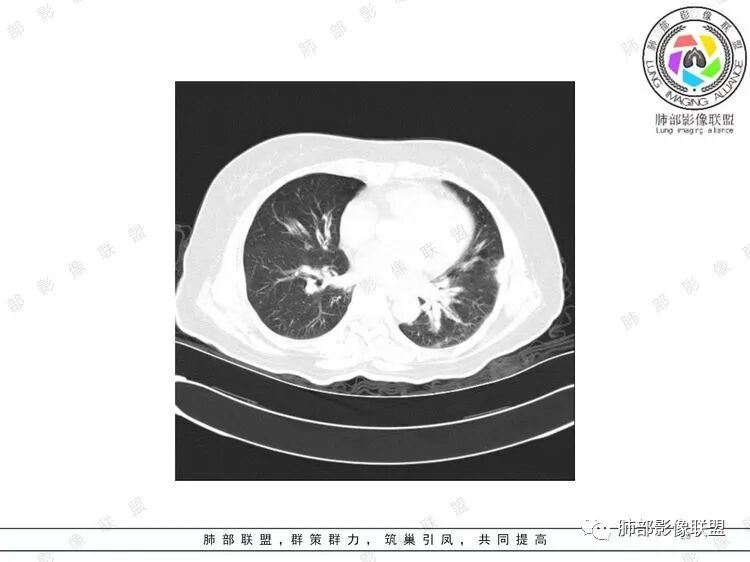

胸CT:双中下肺支气管壁明显增厚,双下肺胸膜下可见实变区。部分病变呈楔形影。

双肺支气管管壁弥漫性增厚,管腔狭窄,下叶为主,伴多发高密度结节影,边缘模糊,双肺支气管血管束明显增粗,临床症状咳嗽低热,有血尿,首先考虑血管炎

支气管壁增厚,两下肺为主,沿支气管血管束分布斑片状、结节状病变,中轴间质增厚。疾病谱可能有:1.气道来源疾病:结核、曲霉、支原体等;2.间质来源疾病:血管、淋巴系统。结合有血尿,使用激素后尿色变淡、抗生素治疗效果差等病史,考虑血管炎可能性大。

影像上:多发结节沿血管分布;双下叶支气管血管束简直增厚,偏血管,支气管通畅

首先肺部气道来源的病变不符合

因为支气管壁增厚,远端应该小气道病变,这个不是,反而是血管增粗明显

加上结节的分布,支持血管相关病变

两肺多发结片影,这个病灶很小,但是中间可见支气管影,支气管炎一般不会包在支气管周围,支气管周围间质可能大,包括血管,淋巴等。一般支气管这样穿行的,被包绕的,血管炎,淋巴瘤等这种间质起源比较多见

支气管壁弥漫增厚